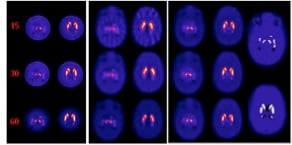

Another example of our current interests is the development of a multi-pinhole collimator (MPH) for use on one gamma-camera head of a general purpose SPECT system in combination with a fan-beam collimator on the second camera head for high resolution / sensitivity imaging of the striatal region of the brain in I-123 DaTscan imaging for Parkinson’s Disease. A rendering of the collimator is shown below followed by reconstructed simulated images of the strata for MPH, Fan, and Combined imaging. These investigations are funded by NIH grant R01-EB022092.

| A. Example XCAT transverse slice multi-pinhole (MPH) collimator noise-free reconstructions through substantia nigra (left) and the caudate and putamen (right) for 15, 30, and 60 angles for VOI over striata. B. Same for low-energy ultra-high-resolution (LEUHR) fan-beam only collimator reconstruction. C. Same for combined reconstruction using MPH and LEUHR fan-beam collimators. D. Matching slices through original XCAT DaTscan source distribution for substantia nigra (top), and caudate and putamen (bottom) with 8:1 striatal to rest of brain concentration ratio, and no activity in the ventricles. Note that separation of caudate and putamen can be seen in combined reconstruction. |